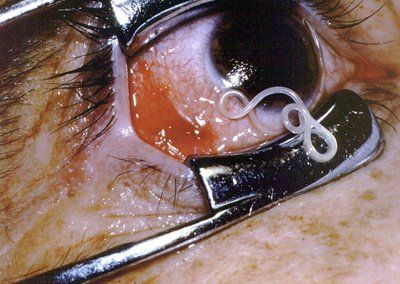

≪MOVIE≫ Worm in the eye removed in Calicut, Kerala